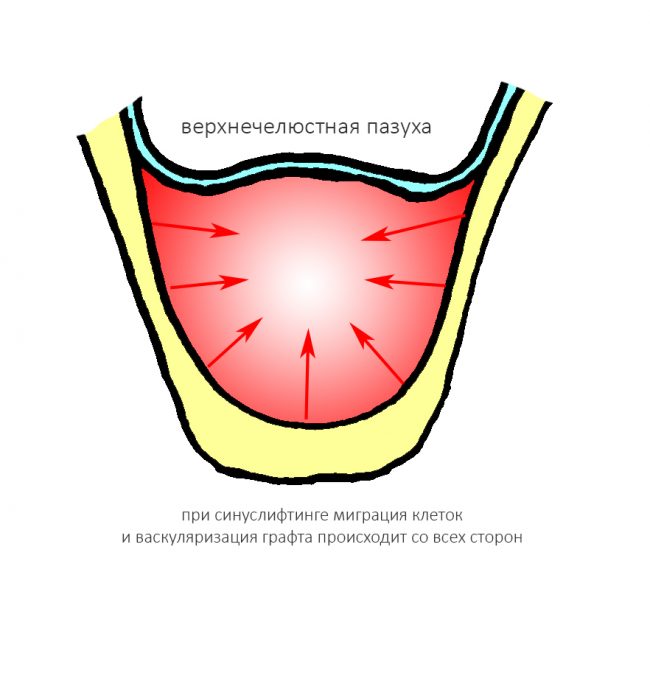

Вывод #2. Чем больше площадь соприкосновения графта с костной тканью, тем больше миграции клеток, тем лучше он прорастает сосудами (васкуляризируется):

Сопоставив понятие периметра с тем, что мы теперь знаем об остеогенезе, легко объяснить, почему при проведении синуслифтинга, в принципе, можно использовать биоматериалы без добавления аутокостной стружки:

Мы имеем дефект с сохранением пяти стенок из шести, с большой площадью поверхности и относительно небольшим расстоянием до центра:

где миграция клеток и васкуляризация идет от периметра к центру со всех сторон и предел роста как таковой, в принципе отсутствует.